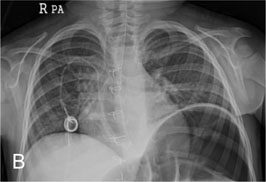

Fig. 1-B

TIVD inserted through Rt. SCV before a removal operation

Fig. 1-B TIVD inserted through Rt. SCV before a removal operation